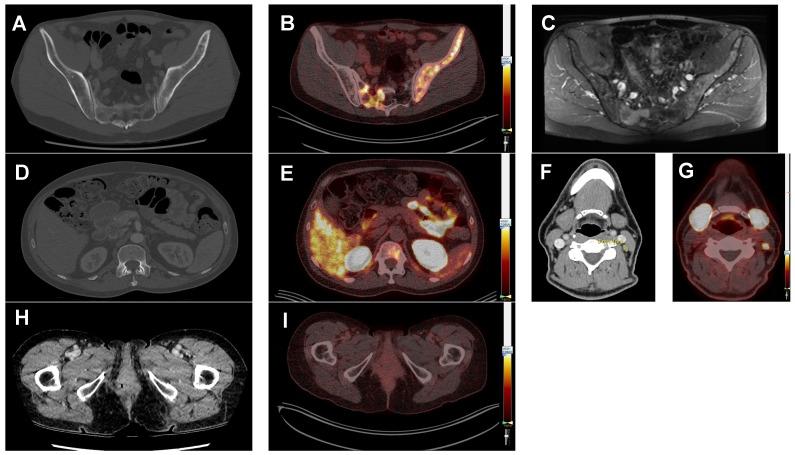

: Treatment options for recurrent and/or metastatic (R/M) adenoid cystic carcinoma (ACC) and salivary duct carcinoma (SDC), major subtypes of salivary gland cancer, are limited. Both tumors often show overexpression of prostate-specific membrane antigen (PSMA). In prostate cancer, PSMA-ligands labeled with Ga or Lu are used for imaging and therapy, respectively. Primary aim of this study in R/M ACC and SDC patients was to systematically investigate Ga-PSMA-uptake by PET/CT imaging to determine if PSMA radionuclide therapy could be a treatment option. : In a prospective phase II study, PET/CT imaging was performed 1 h post injection of Ga-PSMA-HBED-CC in 15 ACC patients and 10 SDC patients. Maximum standardized uptake values (SUV) were determined in tumor lesions. Immunohistochemical PSMA expression was scored in primary tumors and metastatic tissue. Standard imaging (MRI or CT) was performed for comparison. : In ACC patients, SUV ranged from 1.1 to 30.2 with a tumor/liver-ratio >1 in 13 out of 14 evaluable patients (93%). In SDC patients, SUV ranged from 0.3 to 25.9 with a tumor/liver-ratio >1 in 4 out of 10 patients (40%). We found a large intra-patient inter-metastatic variation in uptake of Ga-PSMA, and immunohistochemistry did not predict ligand uptake in ACC and SDC. Finally, PSMA-PET detected additional bone metastases compared to CT in 2 ACC patients with unexplained pain. : In 93% of ACC patients and 40% of SDC patients we detected relevant PSMA-ligand uptake, which warrants to study PSMA radionuclide therapy in these patients. Additionally, our data provide arguments for patient selection and treatment timing. Finally, PSMA-PET imaging has added diagnostic value compared to CT in selected patients.

在 ACC 患者中,SUV 范围为 1.1 至 30.2,14 例可评估患者中有 13 例(93%)肿瘤/肝脏比值>1。在 SDC 患者中,SUV 范围为 0.3 至 25.9,10 例患者中有 4 例(40%)肿瘤/肝脏比值>1。我们发现 Ga-PSMA 摄取在患者间存在很大的转移灶内变异,并且在 ACC 和 SDC 中免疫组化并不能预测配体摄取。最后,在 2 例原因不明疼痛的 ACC 患者中,PSMA-PET 比 CT 检测到更多的骨转移。